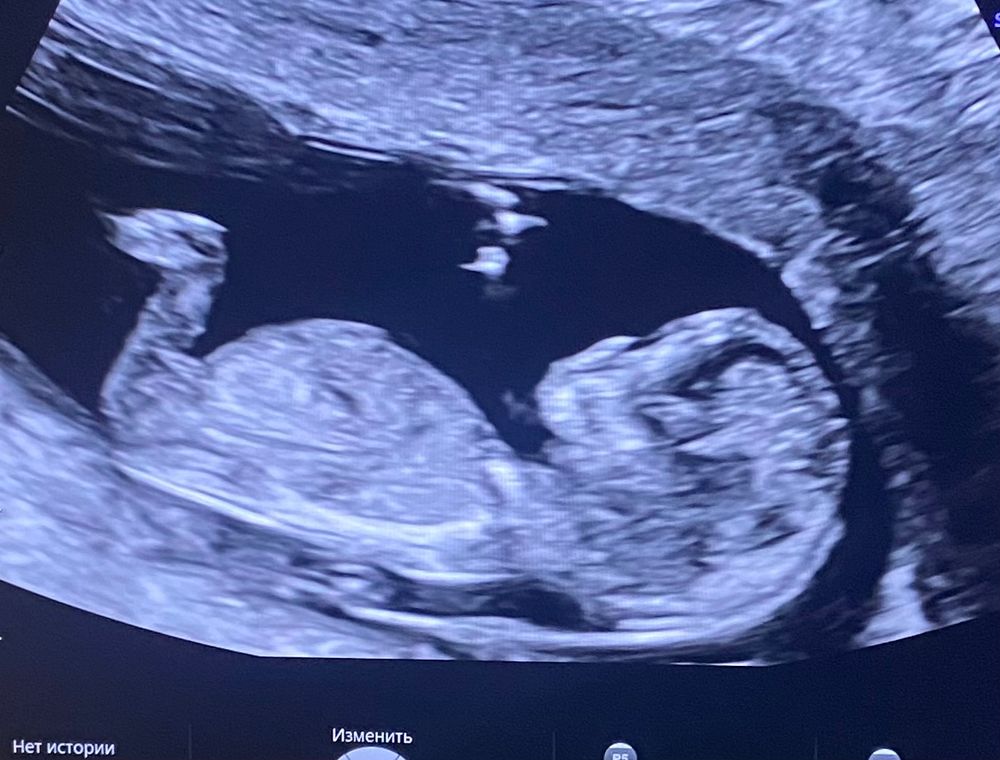

Девочки опытные подскажите( фото 12 недель)

Мне тоже больше склонно видеть девочку, бугорок есть просто ножки рядом, и он меньше 30 градусов

Вообще ножкой закрылась, но если то, что просвечивает через ножку- это оно, то тогда девочка, у мальчиков больше вверх))

Пол в 12 неделек, какова вероятность ошибки? Нужно ли гендер пати?